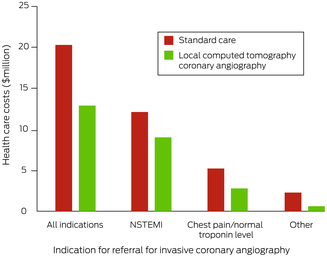

Health care costs

Total estimated health care costs for the 1017 people who underwent ICA in Perth were $20.3 million; substantial costs were associated with aeromedical transfer (data not shown). The estimated costs by indication were $12.4 million for NSTEMI (60.9%), $5.4 million for chest pain with normal troponin level (26.7%), and $2.5 million for other (12.4%) (Box 7). Mean lost productivity for the 612 people of working age was 3.4 days (SD, 3.0 days) and the mean income lost $754.81 (SD, $728.87).

Local computed tomography coronary angiography model of care

Were CTCA undertaken in rural centres, 573 referrals could have been averted (52.7%), the number of metropolitan hospital bed‐days reduced from 4065 to 2308 (43% reduction), and the ICA:revascularisation ratio reduced from 2.6 to 1.6. Total estimated health care costs would be reduced from $20.3 million to $13.0 million (36% reduction) (Box 8). The cost proportion saved was lower for people with NSTEMI as ICA indication ($3.2 million, 26%) than for those with chest pain and normal troponin levels ($2.4 million, 44%) or other indications ($1.6 million, 64%). Not transferring people of working age with non‐severe stenosis would save a mean 3.0 days (SD, 2.6 days) of lost productivity and $619.90 in lost income per patient (SD, $568.00).

We report the first study of CAD severity in people in rural and remote locations of WA referred with non‐urgent indications to metropolitan tertiary hospitals for ICA evaluation. More than one‐third of people in the study had normal coronary arteries or non‐obstructive CAD (< 50% stenosis), all of whom were medically managed. About 75% of people with severe CAD or an occluded vessel underwent revascularisation (389 of 515), but only 7% (nine of 137) with moderate CAD (50–69% stenosis); in total, for every 2.6 ICA assessments undertaken, one patient underwent revascularisation. We also found that undertaking CTCA in rural centres could avert 53% of transfers for ICA by locally identifying people with non‐obstructive CAD who may not require ICA. This would reduce the number of required metropolitan hospital bed‐days by 43%, health care costs by 36%, the ICA:revascularisation ratio from 2.6 to 1.6, and lost productivity by three days per patient.

Box 7 – Total health care costs for 1017 patients from rural or remote Western Australia who underwent invasive coronary angiography in Perth during 2019, by care model

NSTEMI = non‐ST segment elevation myocardial infarction.

Box 8 – Total health care costs for 1017 patients from rural or remote Western Australia who underwent invasive coronary angiography in Perth during 2019, by indication

Care model | |||||||||||||||